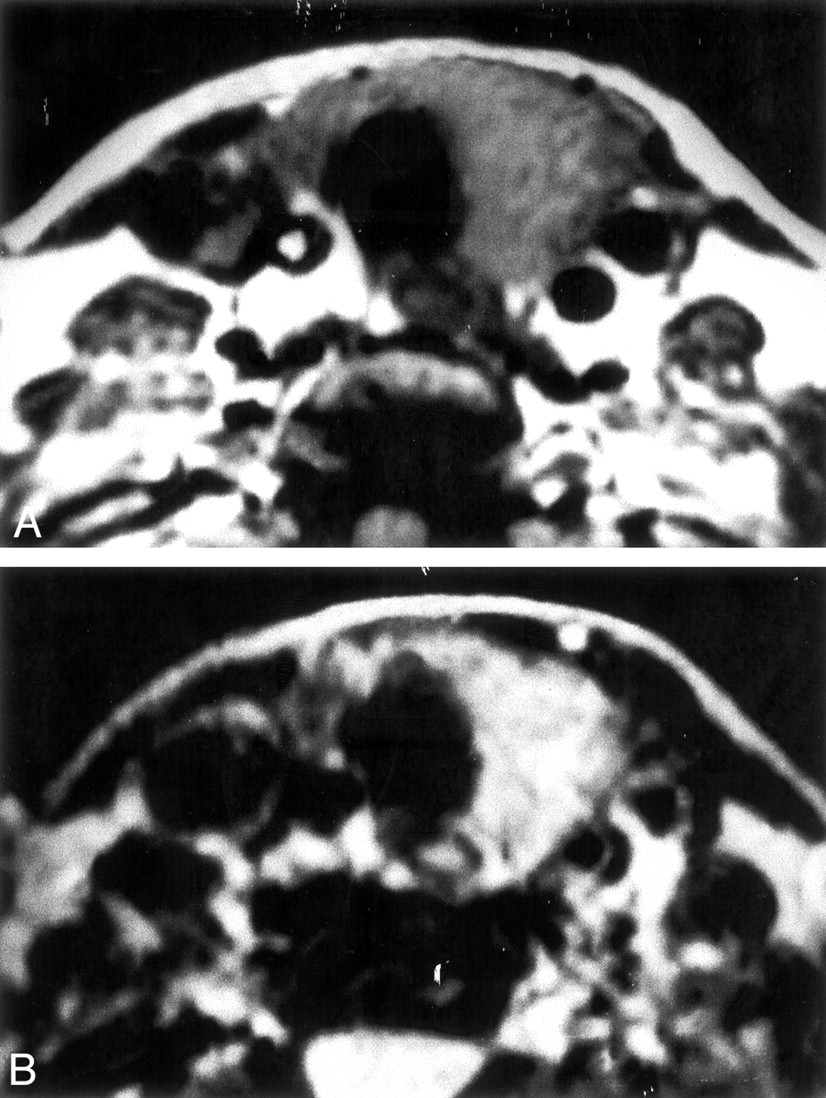

Patient 1. Axial MR images of the neck.

A, T1-weighted image shows mild hyperintensity in the thyroid gland.

B, T2-weighted image shows a more pronounced hyperintensity, compared with muscle, in the thyroid gland.

On MR images, the normal thyroid gland shows homogeneous T1-weighted signal intensity that is slightly greater than that of skeletal muscle. On T2-weighted sequences, the normal thyroid gland is hyperintense to the neck muscles; after the administration of contrast material, the normal gland enhances diffusely and homogeneously. Otsuka et al (7) reported the cases of three patients with subacute thyroiditis. They found the thyroid glands to have slightly irregular margins and a higher than normal T1-weighted signal intensity. They also noted a much higher than normal T2-weighted signal intensity. Our patient 1, who underwent MR imaging, showed mild increased signal intensity of the thyroid gland on the T1-weighted images and more pronounced increase in the signal intensity on the T2-weighted images, consistent with the diffuse inflammatory nature of subacute granulomatous thyroiditis (Fig 5).